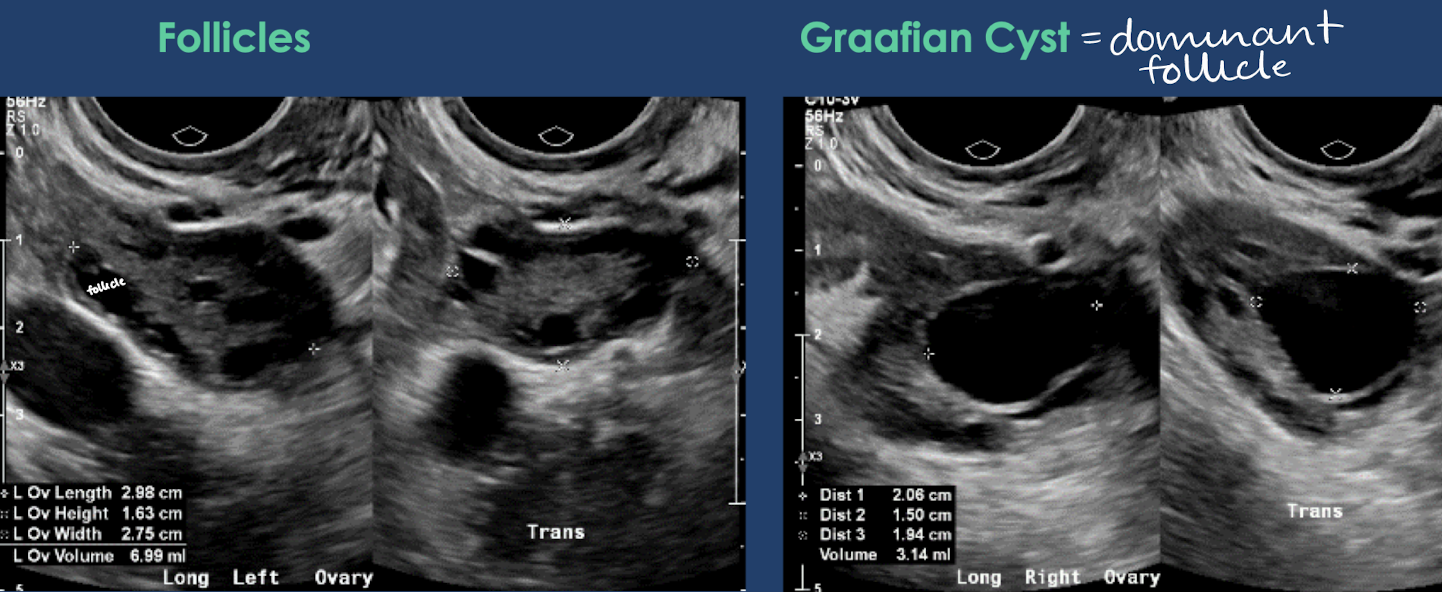

normal ovarian measurements

ovary measures 3-4 cm with volume between 4-6 mL

ovarian follicles are normally visible

dominant follicle (aka Graafian cyst) develops prior to ovulation and measurements ≤ 3 cm